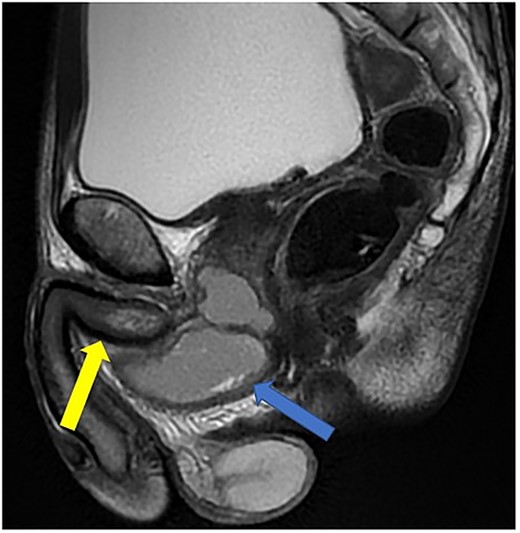

He was put on an empirical course of ciprofloxacin to treat a presumed complicated UTI, and a pelvic MRI was requested. Urine culture grew an Enterobacter cloacae organism. The MRI scan revealed a 7 × 3 cm perineal collection inferior to the prostate and adjacent to the membranous urethra, with increased wall enhancement and fluid with restricted diffusion, with a diagnosis of Cowper’s syringocele (Fig. 3).

Case 2: T2-weighted sagittal MRI image demonstrating a complex, cystic perineal collection (blue arrow), seen in relation to one of the corpus cavernosa (yellow arrow).